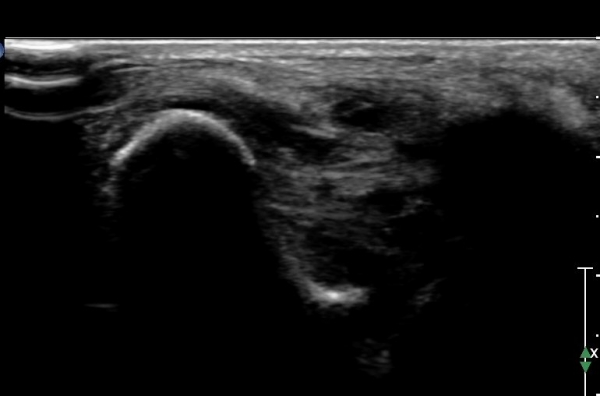

ÇϺΠ½ÅÀü ¶ì(inferior extensor retinaculum) ÀÇ frondiform Àδë Á¾´Ü¸é°Ë»ç¿¡¼­

frondiformÀÎ´ë ½ÉºÎ°¡Áö ÁÖº¯ ¼ö¾×Àú·ù°¡ °üÂûµÇ°í Á·±Ùµ¿ °æºÎÀδ밡 ³Ê¹« ¶Ñ·ÇÈ÷

°üÂûµÈ´Ù(»çÁø 5, 6, 7).

frondiformÀδëÀÇ Àú¿¡ÄÚ ºÎÁ¾°ú °Å°ñÇÏ °üÀý °£°ÝÀÌ ¹ú¾îÁ® ÀÖ´Ù(»çÁø 8, 9).